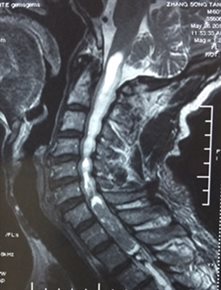

尹xx,女,35岁

患者因“突发双下肢无力3天,加重1天”入院

诊断:颈胸段椎管内髓内肿瘤

入院时患者双下肢不能行走,入院后完善相关检查,择期行手术治疗。

FullSizeRender (4)FullSizeRender (5)

术前                                   术后